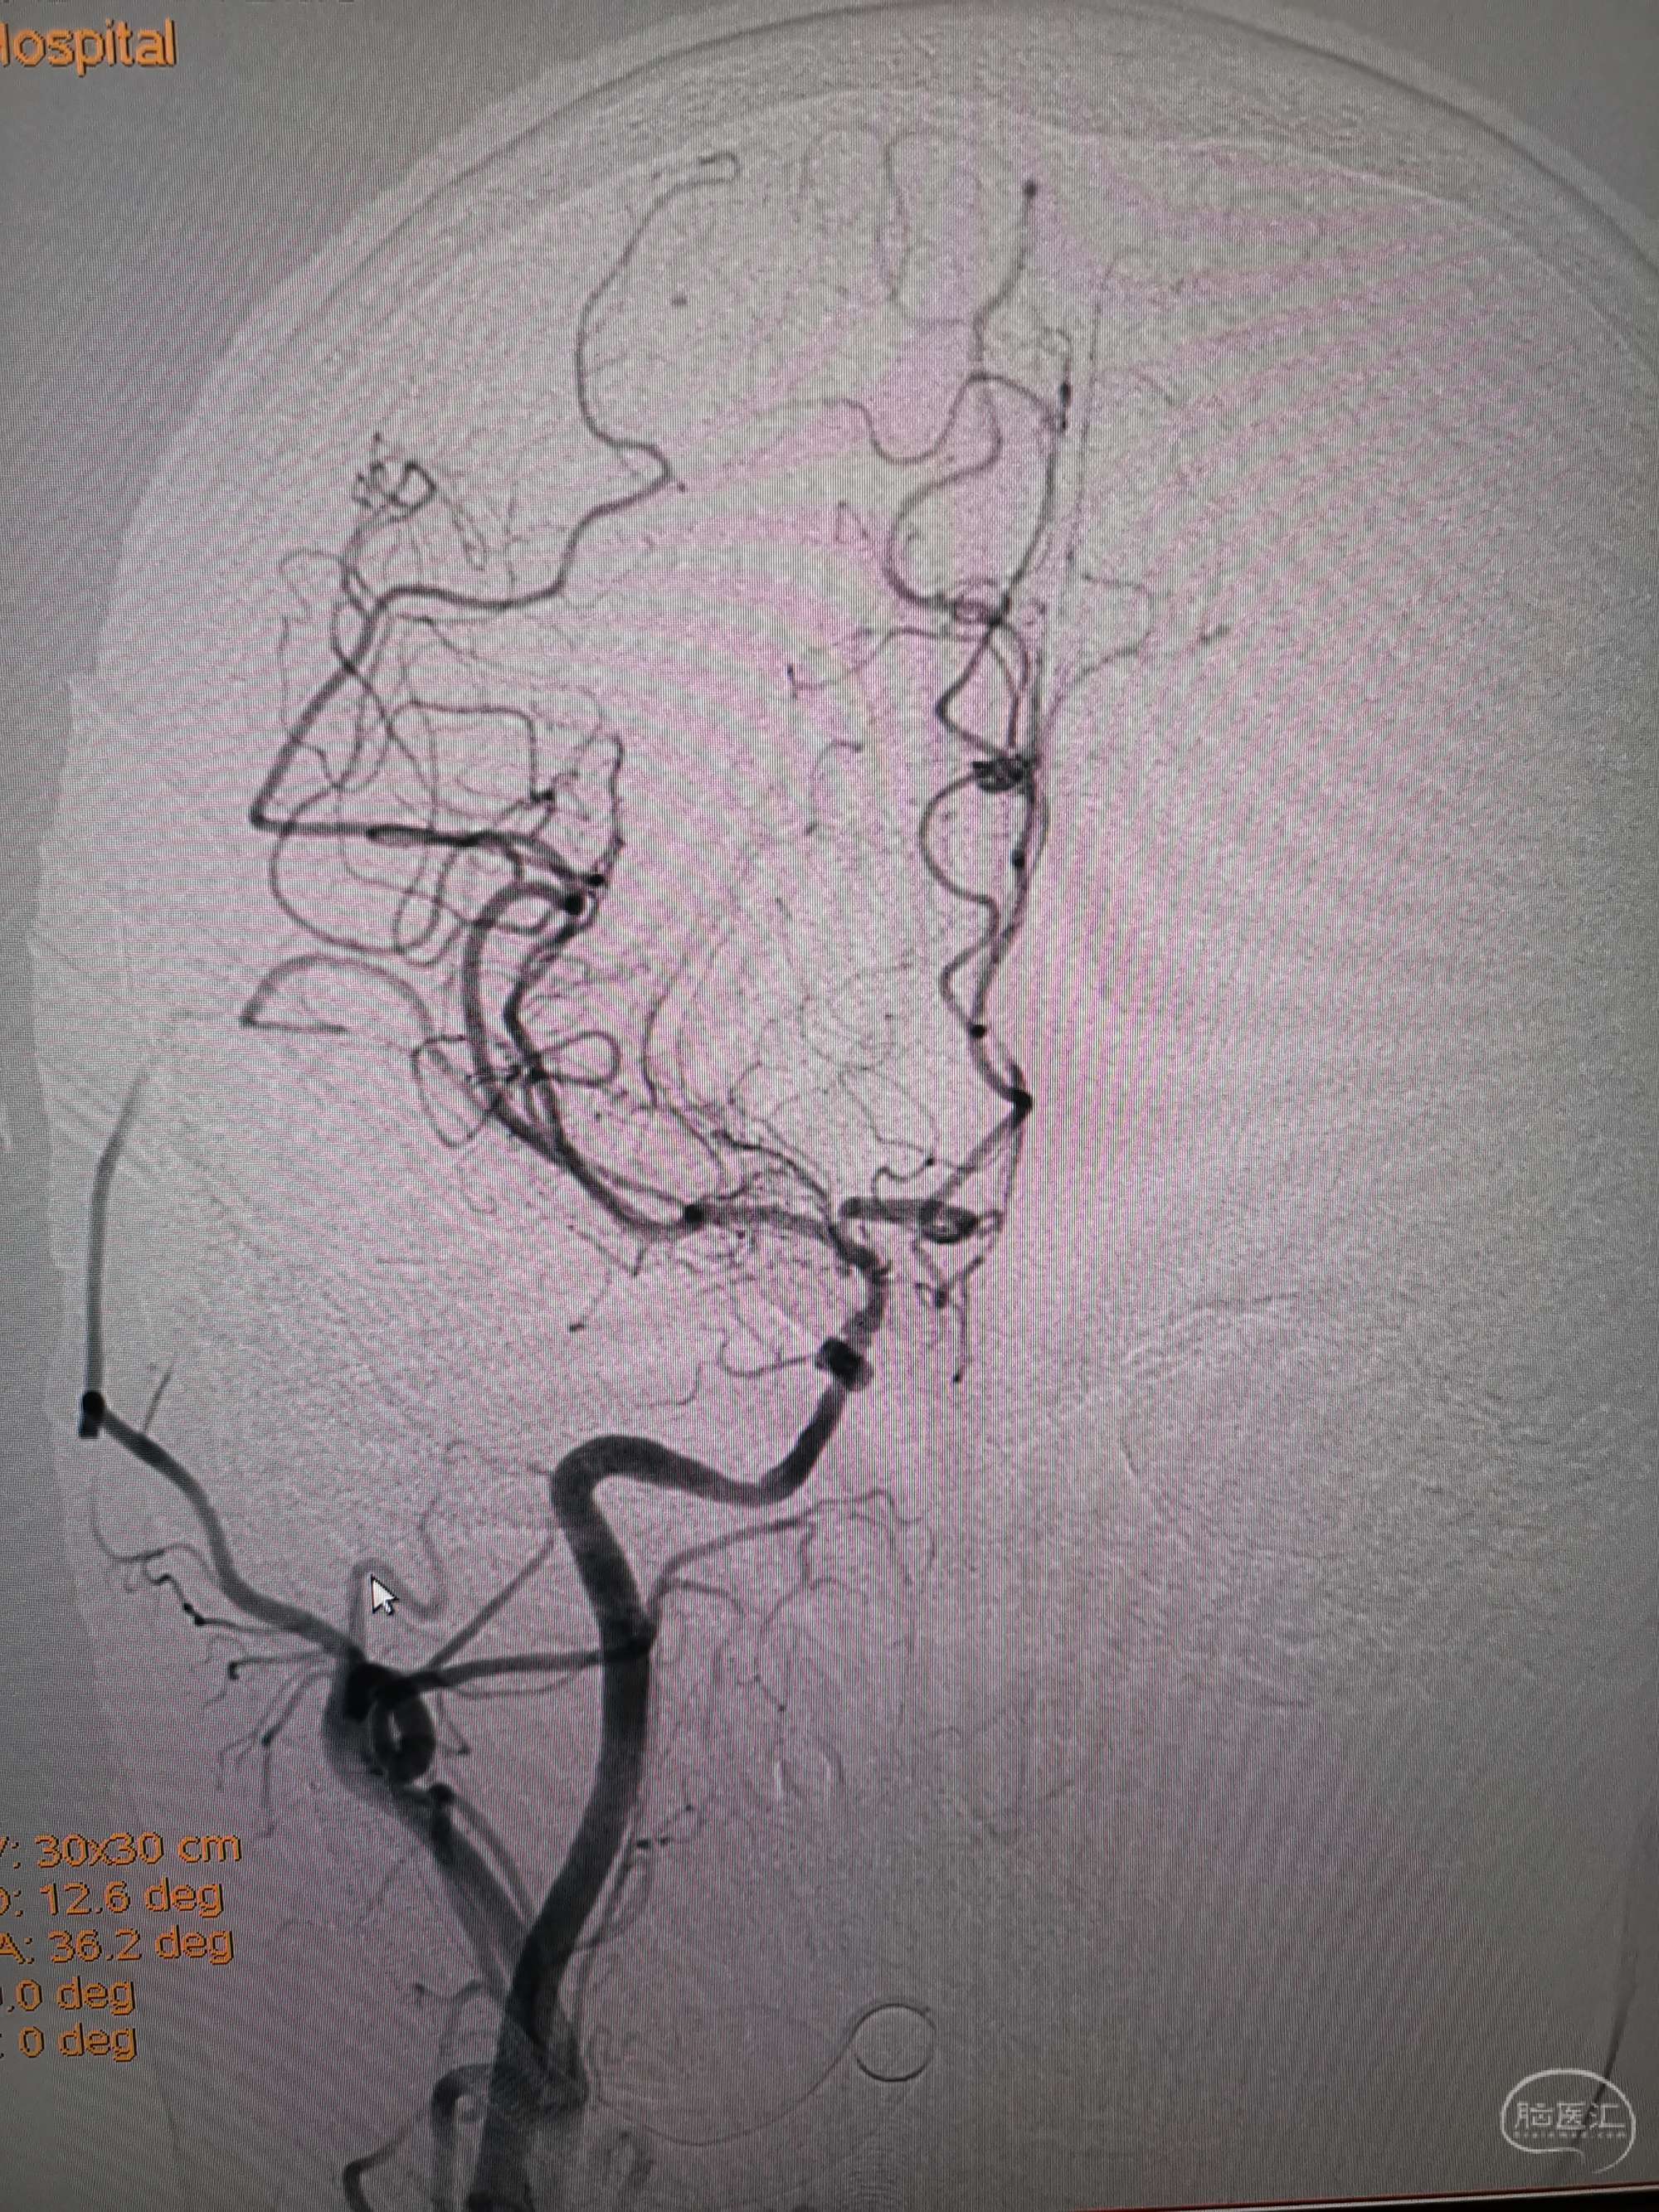

入院造影影像

男性,56岁,突发意识嗜睡,言语不能,吞咽困难,右侧肢体偏瘫于8月7日收住院。入院后急诊给予阿替普酶静脉溶栓,溶栓后造影显示双侧椎动脉闭塞,后交通未开放,仅右侧椎动脉有一穿支向基底动脉少量供血,考虑为原位狭窄后急性闭塞。核磁显示脑干及小脑多发急性梗死灶,拟双抗3周后行再通治疗。给予阿司匹林100mg及氯吡格雷75mg双抗3周后患者吸入性肺炎并反复消化道出血,停双抗治疗给予抗炎、抑酸药物治疗后感染控制,消化道出血停止,查血栓弹力图后重启双抗治疗一周,病情稳定,于今日在全麻下行左侧椎动脉再通术,手术顺利,详细情况如下